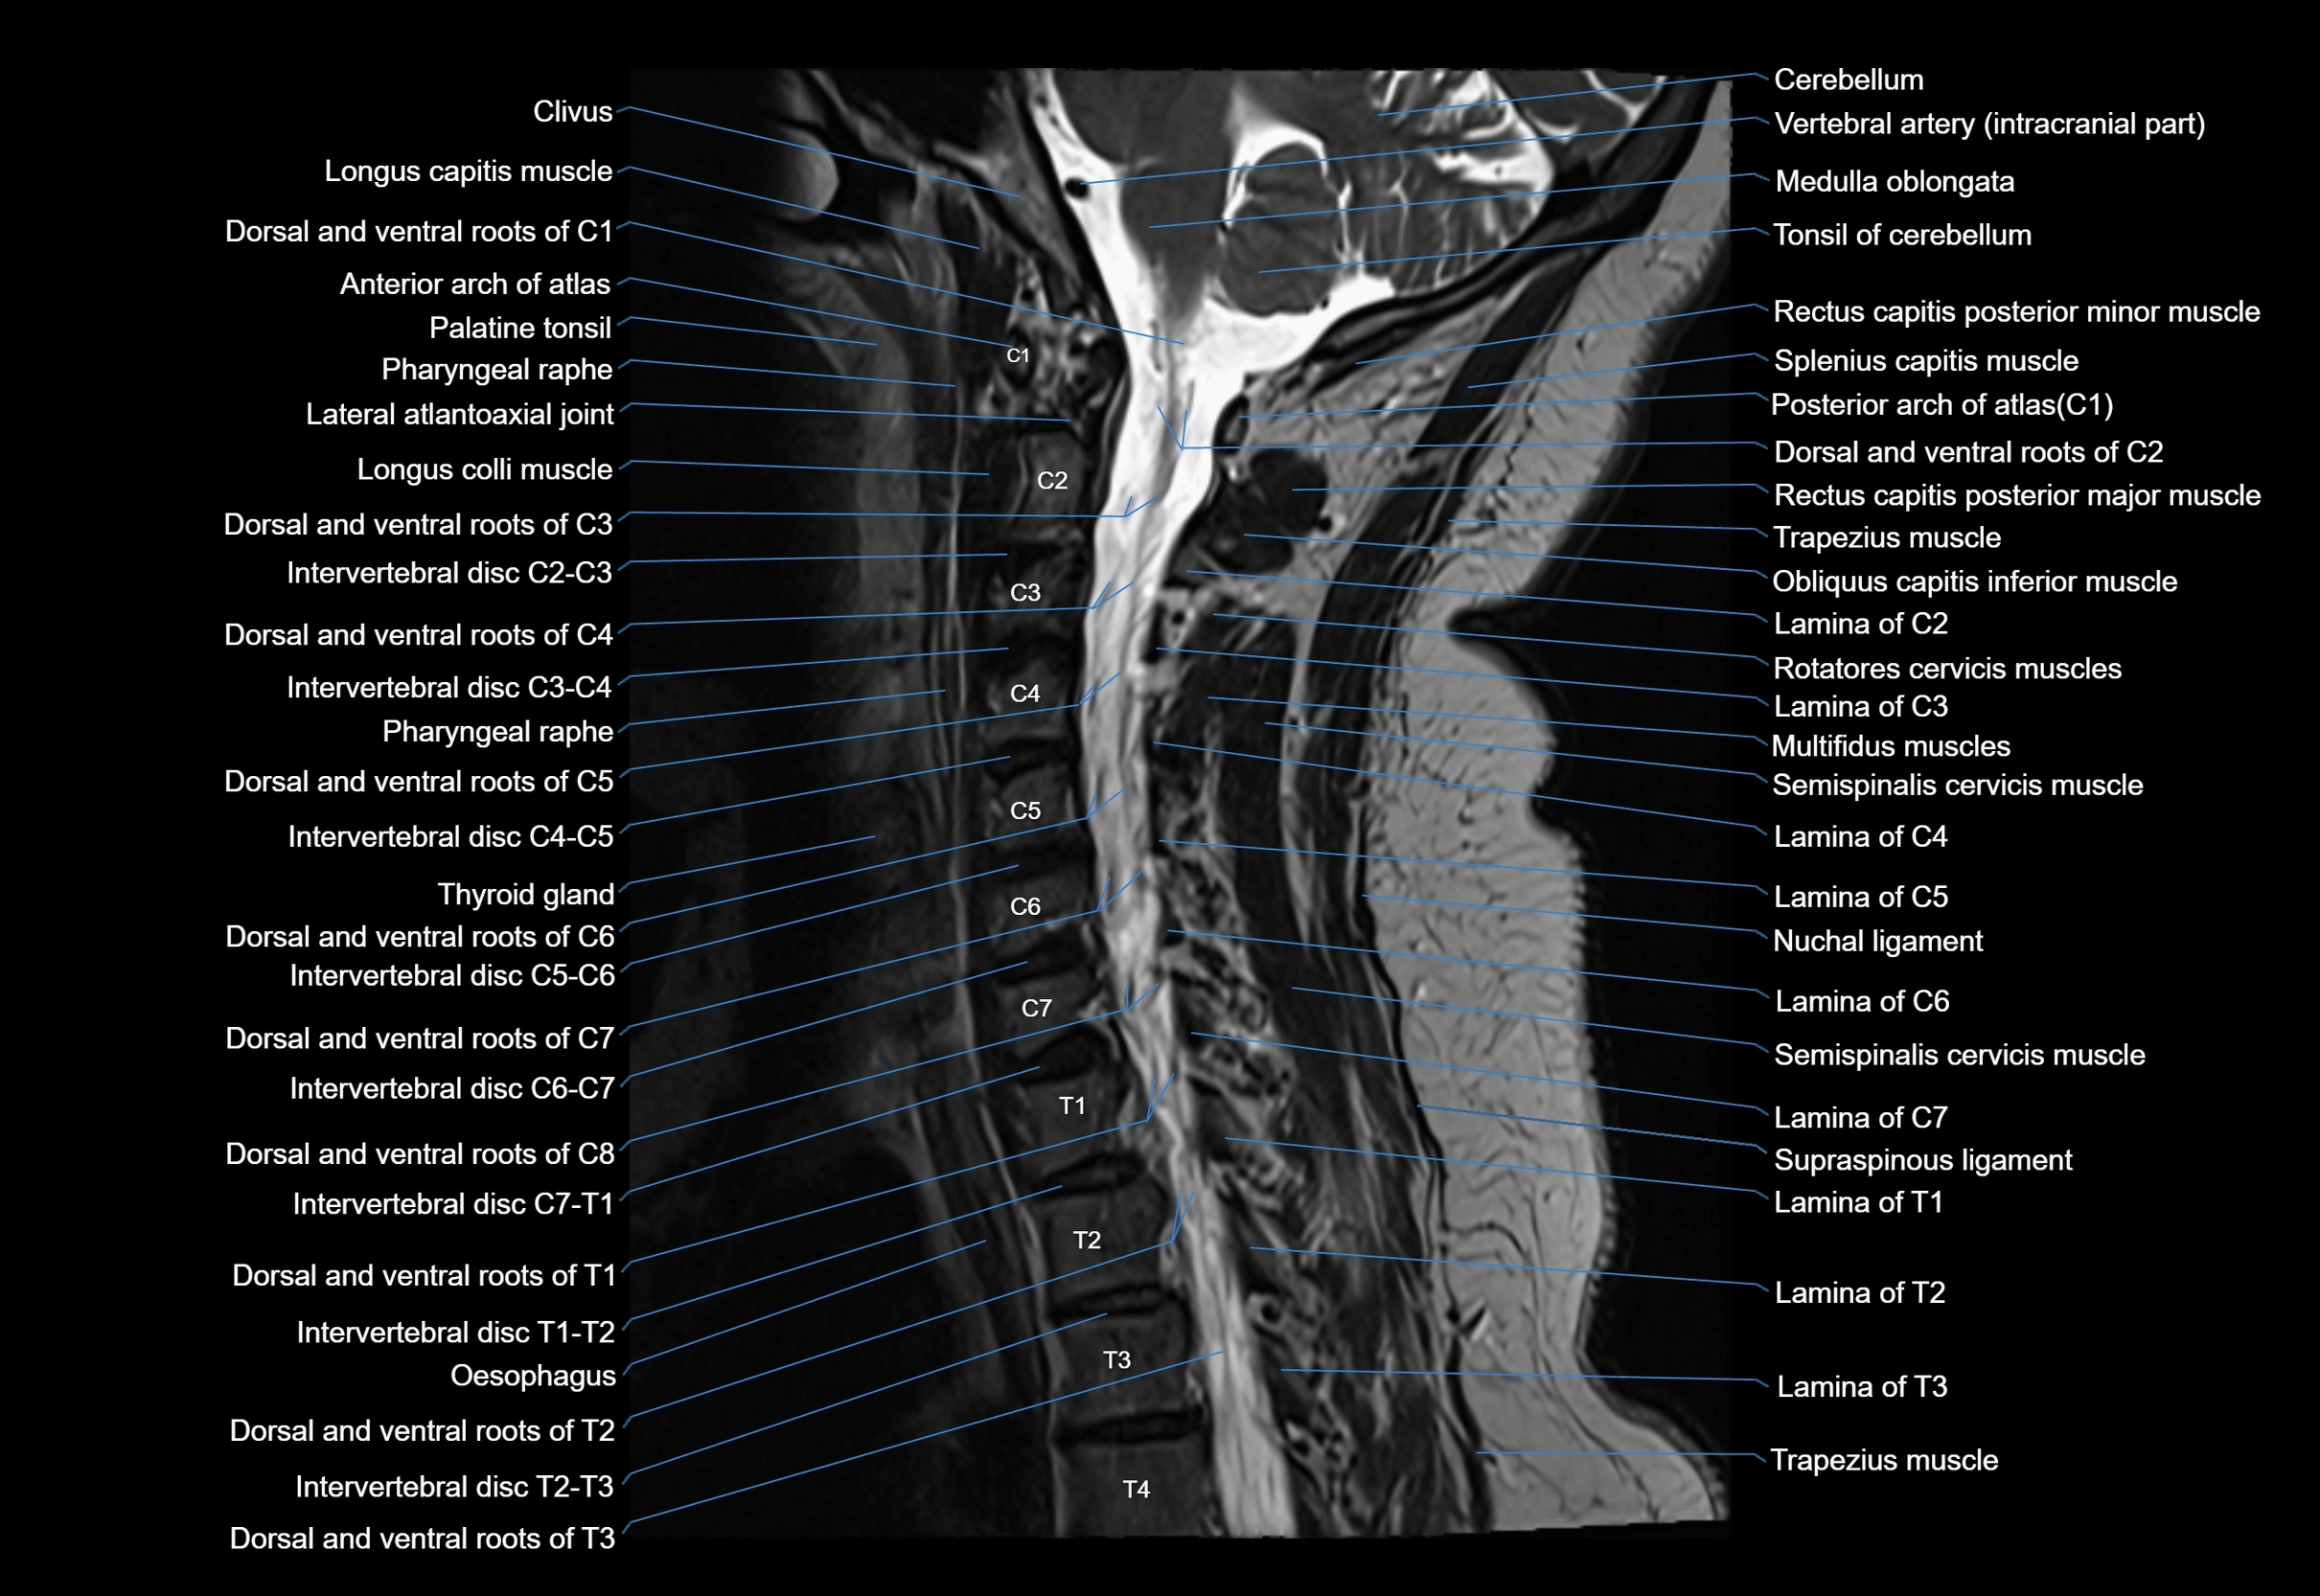

MRI appearance

T1-weighted images:

• Annular epiphysis: Low signal cortical rim at the vertebral margin

• Adjacent marrow: Intermediate-to-high signal in the vertebral body

• Disc interface: Clear delineation between bone and annulus

T2-weighted images:

• Annular epiphysis: Low signal intensity line

• Endplate cartilage (in younger patients): Intermediate signal

• Intervertebral disc: High signal nucleus pulposus

STIR:

• Annular epiphysis: Low signal cortical rim

• Adjacent marrow: Suppressed fat signal with preserved bony outline

• Utility: Highlights marrow and endplate interface in developing spine

MRI image

image